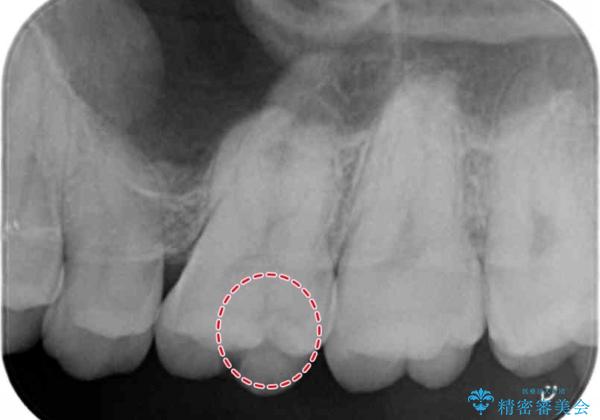

検査の結果、昔治療した樹脂の詰め物と歯の間に虫歯ができていることが確認されました(二次う蝕といいます)。

視診だけではわかりづらいですが、レントゲン画像にて昔の詰め物の下に虫歯があることがわかります。

以前樹脂を詰めた結果再び虫歯ができてしまっていることから、同じ治療は同じ結果になる可能性があるため今回はアプローチを変えてセラミックインレーで修復処置をしていくこととなりました。